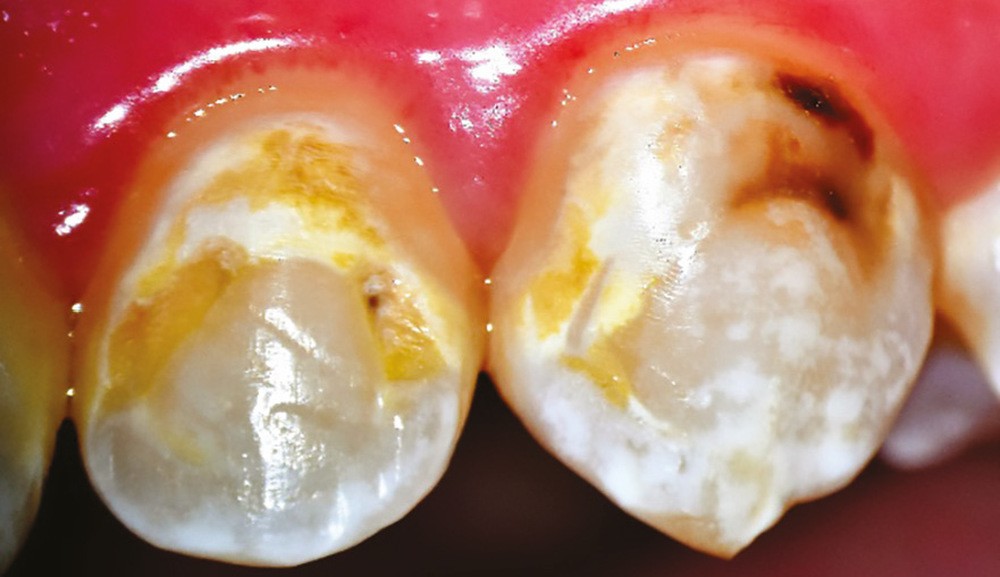

• Traitement micro invasif : il s’agit essentiellement de l’érosion/infiltration (fig. 5), mais une alternative peut également être utilisée pour les mêmes indications : le traitement de micro abrasion (fig. 6). L’indication première de cette technique est d’arrêter la progression des lésions carieuses non cavitaires lors d’une déminéralisation de l’émail (ICDAS 2) ou cavitaires au niveau de l’émail sans déminéralisation de la dentine sous-jacente (ICDAS 3) d’un patient à faible risque carieux.

Le principe d’érosion infiltration consiste à infiltrer par capillarité l’émail déminéralisé avec de la résine. La surface dentaire doit être préalablement traitée par un acide afin d’ouvrir les porosités de surface de l’émail et permettre une meilleure pénétration de la résine. Le processus carieux sera stoppé en bloquant la pénétration des acides cariogènes et la structure dentaire sera préservée.

Cette technique est réalisée en une seule séance clinique, et présente l’avantage d’être peu invasive et indolore. Cependant, le problème de l’accessibilité dans les lésions proximales est un facteur qui limite l’utilisation de ces thérapeutiques. Le recours à un élastique orthodontique quelques jours avant la mise en place de la résine est une solution intéressante pour améliorer l’accessibilité et traiter les lésions de déminéralisation en proximal. Aujourd’hui, ces thérapeutiques sont également utilisées dans le traitement esthétique des taches blanches vestibulaires de l’émail, la mise en place du produit étant facilitée dans ces situations cliniques.